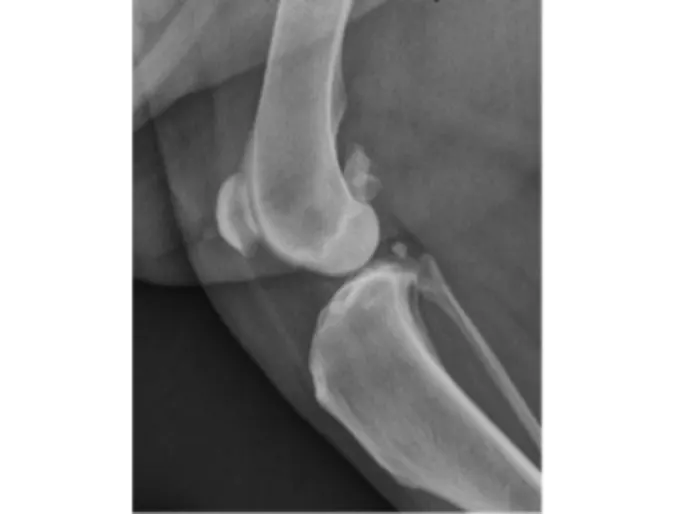

Figure 1. Radiograph of a normal canine stifle (knee joint) with no arthritis.